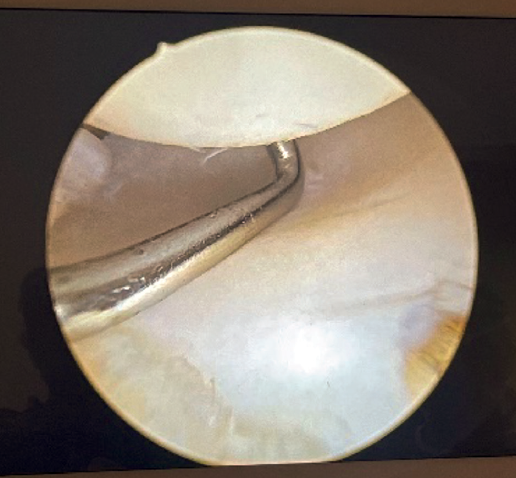

Visioning for lateral complex plication is made through the posterolateral portal. From this portal we access the lateral elbow groove to visualize the posterior part of the radiocapitellar joint. It will also allow us to examine the Osborne-Cotterill lesion component and determine the degree of posterolateral instability by applying varus and supination to the forearm. With this maneuver we can observe how the radial head undergoes subluxation posteriorly and the joint line opens (Figure 2).

If tension is now applied to both sutures and we observe from the posterolateral portal, the radiocapitellar joint is seen to close following plication (Figure 8).